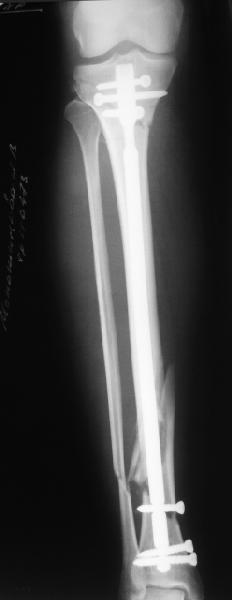

Re: Проксимальный и дистальный переломы tibia

Сделали все-таки стержнем. На всякий случай просверлил дополнительное проксимальное отверстие, так что получилось три 45-градусных винта.

В дистракторе провеи спиц поболше в прокисмальном отделе, чтобы не разобщить фрагменты при сгибании колена. Комментарии и критика приветствуются.

We proceeded with nailing using a small wire distractor, with few wires at the proximal end to prevent displacement with forced knee flexion. Images attached. Comments and critics are welcome.